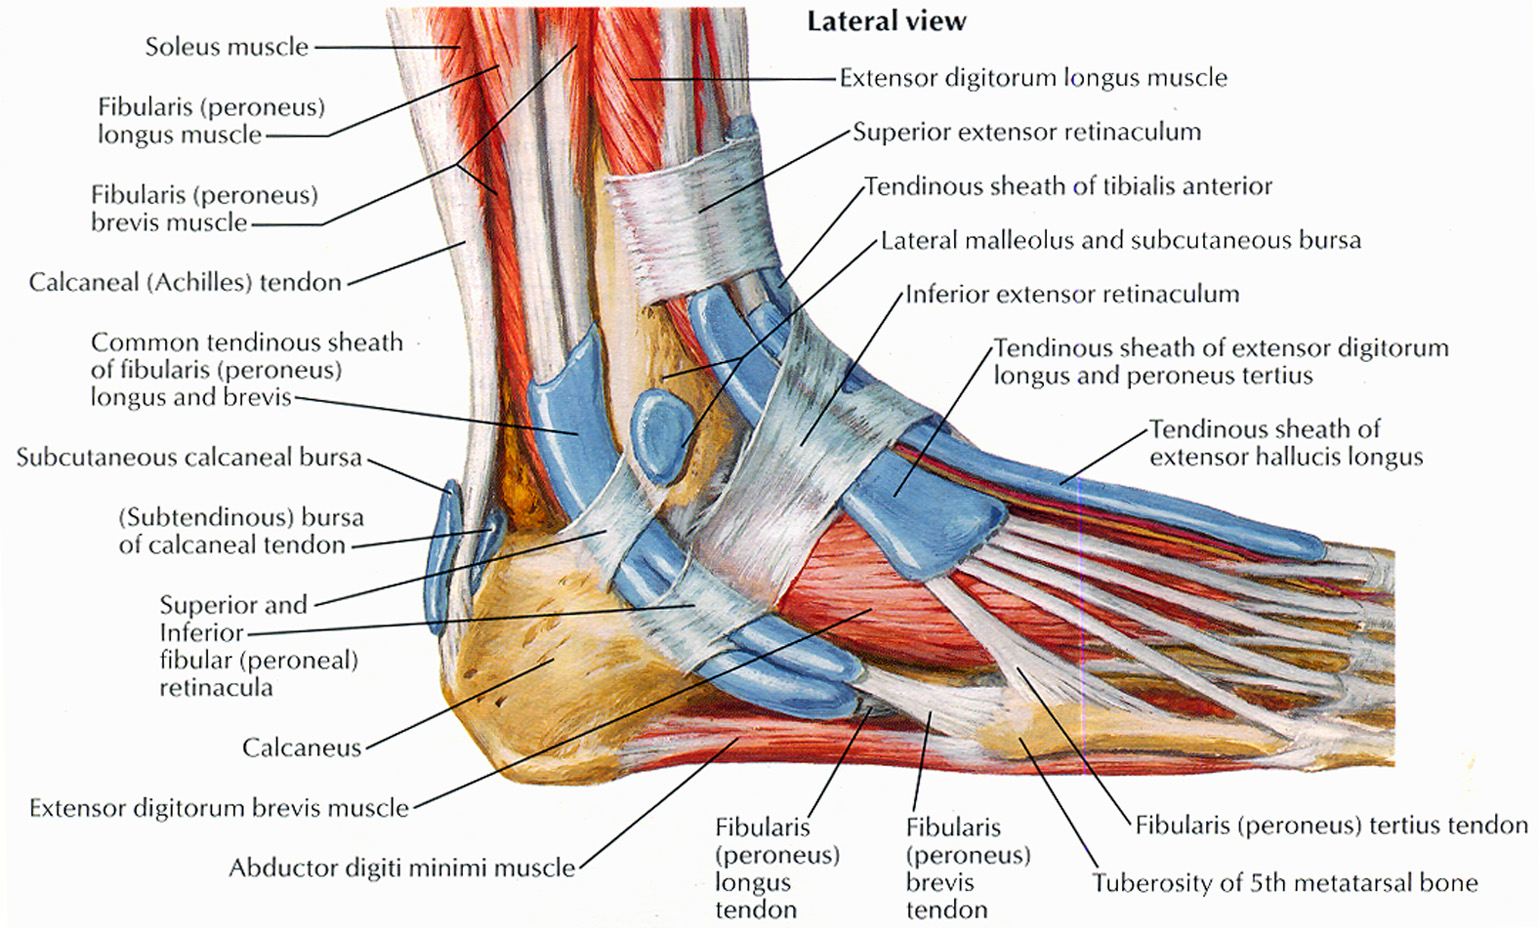

ibiologia.comfoot anatomy muscles ligaments tendons bones feet

ibiologia.comfoot anatomy muscles ligaments tendons bones feet

Muscolo Estensore Breve Delle Dita Del Piede (o Pedidio

www.pinterest.chpiede dita estensore muscolo legamenti breve collo muscoli medicinapertutti anatomia caviglia umano lungo tenosinovite dolore plantari muscolare scheletro salvato questi

www.pinterest.chpiede dita estensore muscolo legamenti breve collo muscoli medicinapertutti anatomia caviglia umano lungo tenosinovite dolore plantari muscolare scheletro salvato questi